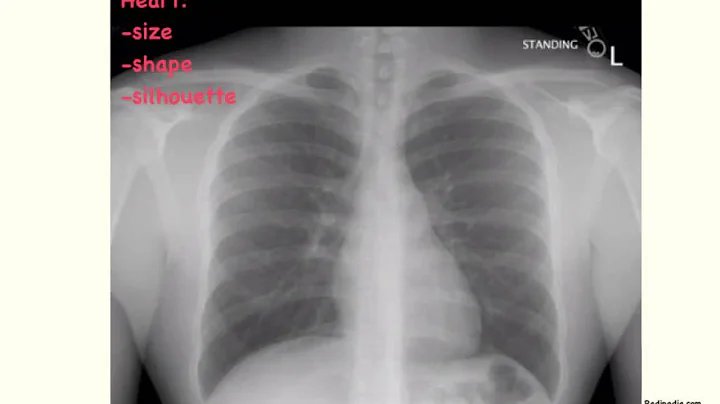

The ABCDE's to reading a chest xray! A: Airway. Look at the airway. It should be midline. Tumors, tension pneumothorax, large ...